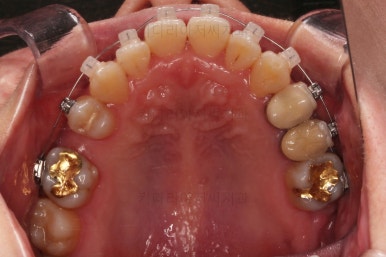

윗니 임플란트 할 자리는 적절히 계속 맞춰줍니다.

중앙선도 점점 맞아지고 있어요.

임플란트 할 공간도 여유롭게 마련이 되었네요.

임플란트는 뿌리 부분 식립 -> 3~6개월 기다림(뼈와 임플란트가 단단히 붙을 시간이 필요) -> 머리 부분을 완성하고 마무리

따라서 교정치료가 100% 끝나기 전에, 임플란트 공간만 마련되면 바로 식립을 하게 됩니다.

임플란트 뿌리 부분이 먼저 식립되었고요.